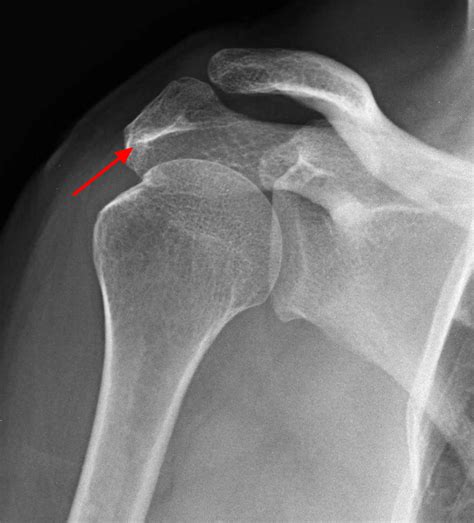

A bone spur is a bony projection that develops along bone edges. In the shoulder, bone spurs can form on the acromion (the highest point of the shoulder blade), the humerus (upper arm bone), or the clavicle (collarbone). These spurs can cause pain and limit shoulder movement, especially when they rub against tendons, ligaments, or other bones.

• Imaging Tests: Diagnostic imaging tests, such as X-rays, CT scans, or MRI scans, can help visualize the bone spur and assess the extent of the damage. These tests provide detailed images of the shoulder joint and surrounding tissues.

X-ray Uses radiation to produce images of the bones. Identify bone spurs and assess bone structure.